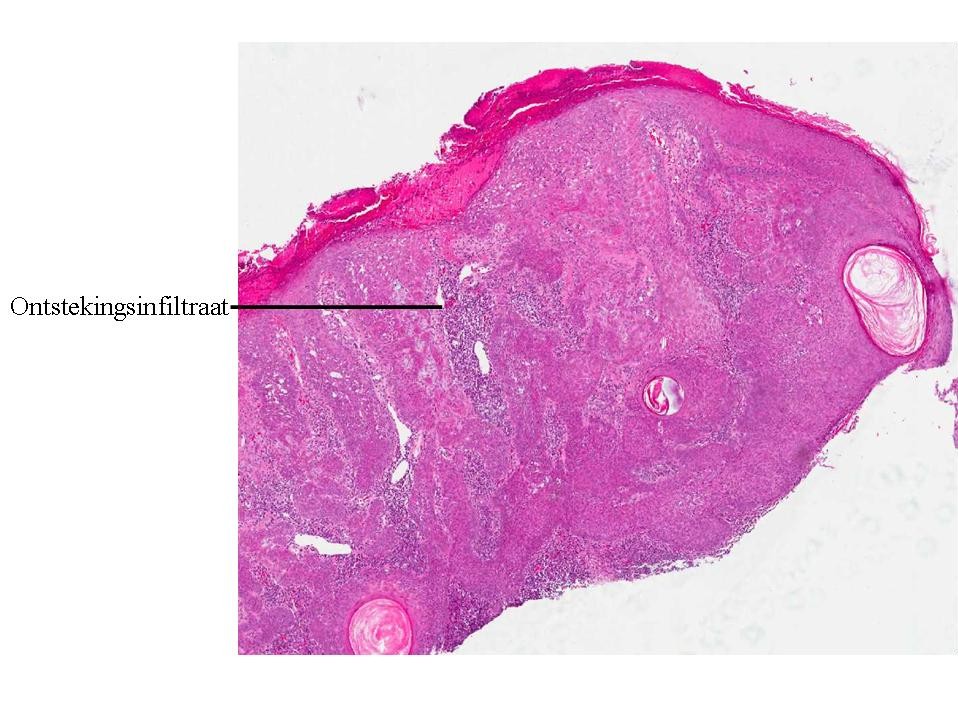

Histologie:Het histologisch beeld wordt gekenmerkt

door een scherp begrensde exofytisch of endofytisch groeiende tumor. Meestal

is er hyperkeratose en een papillomateus verbrede epidermis. De hyperkeratose

en de neiging van de retelijsten om te vergroeien, hebben de vorming van pseudo-hoorncysten

tot gevolg. De tumor is opgebouwd uit opvallend kleine spinale cellen. Basale

hyperpigmentatie is er in een derde van de gevallen. De epidermis toont geen

cytonucleaire atypie. Meestal zijn er geen afwijkingen in de dermis. In de dermis

van een geirriteerde verruca seborrhoica wordt echter een uitgebreid rondkernig

ontstekingsinfiltraat gezien met grensvlakactiviteit en soms met dyskeratotische

keratinocyten. Karakteristiek zijn de zogenaamde “squamous eddies”, nesten van

keratinocyten. Het Borst-Jadassohn type, ookwel het clonale type, is te herkennen

aan intra-epidermale nesten van spinale cellen.